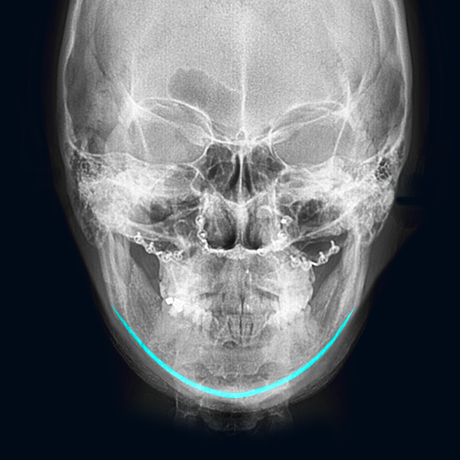

• Before

사각턱 수술 후

울퉁불퉁하고 뭉툭해진 턱선